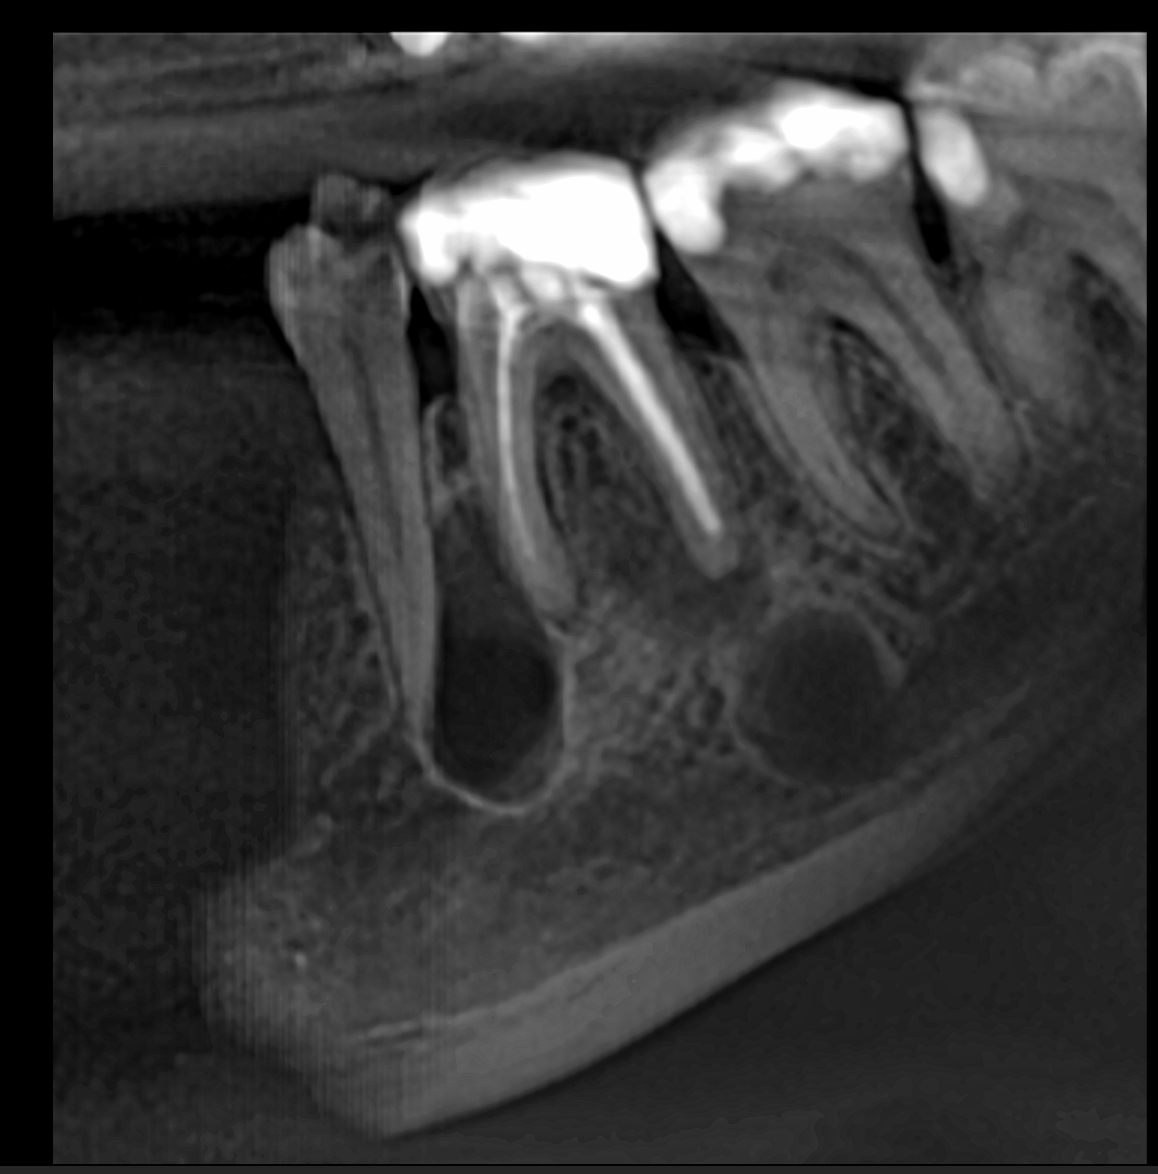

Fig. 1: 2D image generated from the DEXIS OP 3D scan, showing multiple bone lesions.

The patient was asked to search for a centre in his area with the DEXIS OP 3D unit, which provides high-quality images, and to request a 5 × 5 scan in endodontic mode, because it has the highest level of detail. A 2D view was generated from the scan to obtain a preview of the situation (Fig. 1). This showed a large lesion at the level of the mesial root between the molar and the premolar, a smaller lesion under the distal root, a minor lesion at the apex of the mesial root and a large lesion under the distal root at the lower level of the mandible. The question was whether this was one lesion or multiple lesions and one pathology or several.

After adjusting the horizontal and vertical axes according to the axis of the distal root, we could see clearly that the lower bone lesions were well defined (Fig. 3). The clear separation between the lesions, which was evident in the coronal and sagittal views, indicated that they were two different pathologies. The periodontal ligament of the mesial root was present and uninterrupted, marking the separation between the lesion located between the molar and premolar and the mesial root of the molar (Figs. 4a–d & 5). This again confirmed a clinical situation with two kinds of pathologies. The large bone lesions were due to the mastocytosis, and the apical infection of the roots was due to failed root canal treatment.

Figs. 4a–d: After adjusting the axial view according to the roots, the extent of the lesions and the separation between the lesions could be seen clearly.